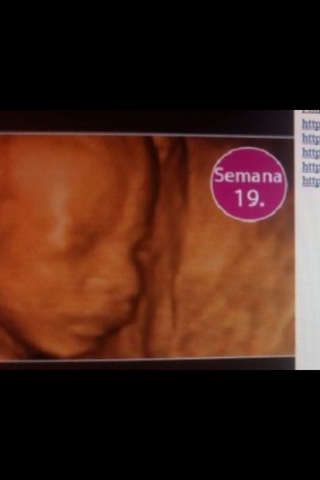

Él bebe ya puede oír los latidos del corazón de la madre

Si él bebe es una niña ya tendrá en sus ovarios huevos primitivos

Su cerebro está desarrollando sus sentidos del gusto, tacto, olfato, audición, visión y tacto

Ya se puede saber el sexo del bebe